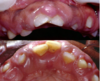

Which systemic disease manifests like this?

Crohn Disease

- Patients can also get angular cheilitis

- Above the Linear ulceration, can see a flap like structure which is the hyperplastic margin